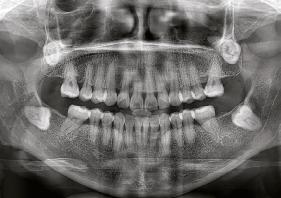

en paciente adulto tratado con extracciones de primeros molares permanentes. Reporte de caso

Dentista y Paciente 52 Sonriendo al futuro